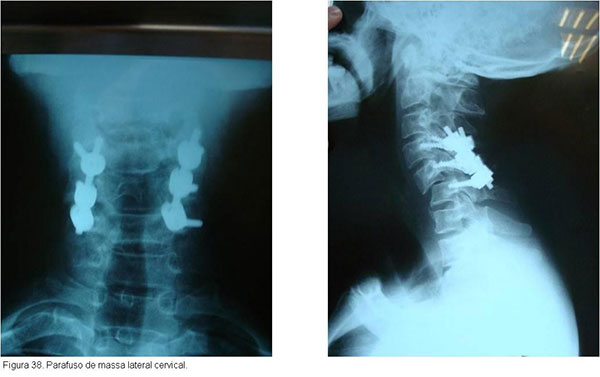

As fraturas cirúgicas da região cervical são estabilizadas com amarrilhos, placas e parafusos, sempre associados à enxertia óssea para facilitar a artrodese. O uso de estabilização anterior e/ou posterior depende do tipo de fratura.(figuras 37, 38, 39)